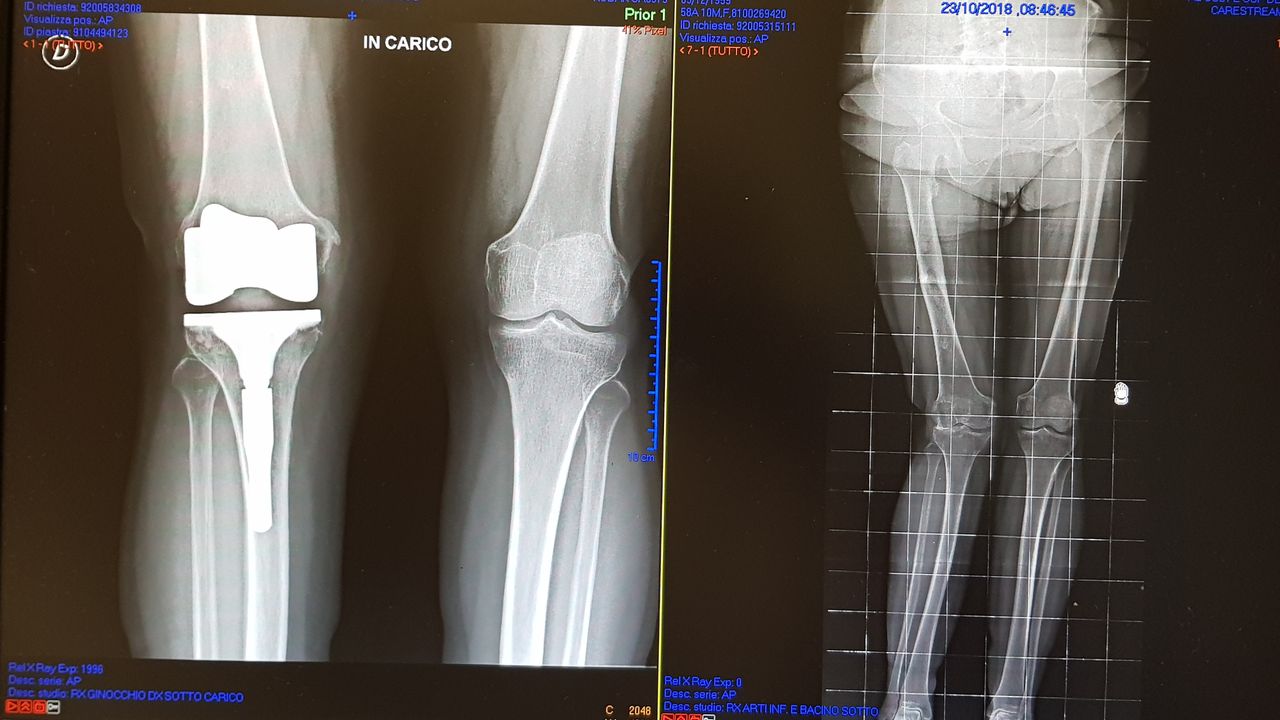

Da quando ha preso servizio presso l’Ospedale del Delta si è sempre occupato della chirurgia protesica del ginocchio sia monocompartimentale che totale acquisendo esperienza anche sulle tecniche basate sulla navigazione assistita che sull’impianto di protesi custom-made. Di routine esegue interventi di chirurgia artroscopica per il trattamento delle patologie meniscali e cartilaginee e di ricostruzione del legamento crociato anteriore mediante varie tecniche